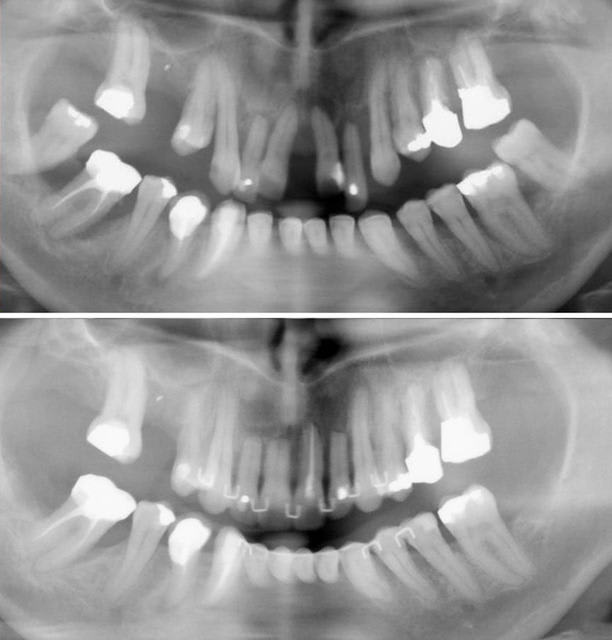

Quoi qu'il en soit, voici les derniers clichés.

Il ont été pris 1 an après la fin du traitement. Attelles de Genon et gouttière de protection supérieure nocturne à porter "à vie".

C'est le statu quo.

Ma question demeure : 21 est moins résorbée que les autres, est-ce dû au traitement radiculaire où à la "pêche" apicale qui a offert une moindre résistance à l'ingression ?

J'aurais aimé que nos experts répondent avant de voir qu'il y a effectivement une différence, mais puisque tu m'as demandé la pano, je m'exécute..

Cette théorie est la théorie classique et je me faisais le reproche d’avoir bêtement oublié de faire traiter en préventif les autres incisives pour ce cas extrême lorsque j’ai lu dans la Revue d’ODF que ce n’était pas indiqué (Samadet V. Entretien avec Pierre Matchou : à propos des résorpions radiculaires liées au traitement d’orthopédie dent-faciale. Rev Orthop Dento-faciale 2007 ;41 : 256).

D’après Pierre Matchou, il n’y aurait pas de participation pulpaire au problème de la résorption tant que la dent est vivante

Pourtant, le résultat ici montre une différence nette au niveau apical.

Faudrait-il expliquer ici la non résorption de la 21 par le granulome apical préexistant qui offrirait une moindre résistance osseuse à l’ingression ?

Pour moi, la question est toujours ouverte. Qu’en pensez-vous ?